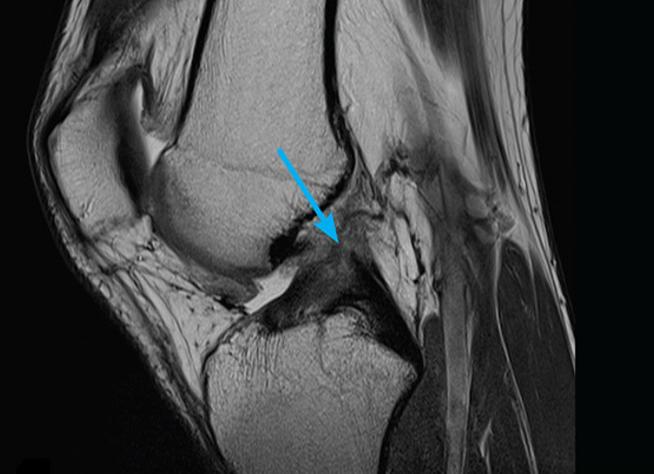

Что показывает исследование

Имеется связь между тем, что показывает и как проходит МРТ коленного сустава. Исследование может выявить разрыв мениска. На МРТ данная хрящевая прокладка будет иметь нечеткий контур. Фото МРТ здорового коленного сустава содержит изображение мениска в виде четкого черного треугольника.

Исследование может показать как растяжение, так и разрыв связок. При этом аппаратура в состоянии фиксировать как частичный, так и полный разрыв. Исследование выявляет присутствие жидкости около связок коленного сустава. МРТ хорошо фиксирует дистрофические явления в хрящах, что с высокой точностью позволяет выявить у пациента артроз суставов.